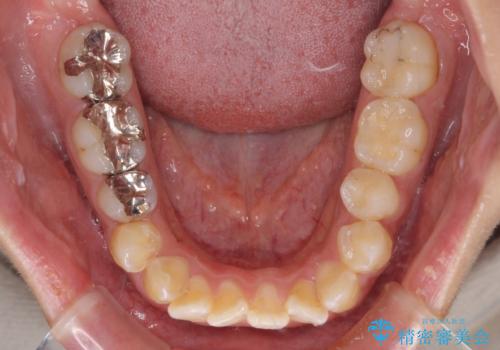

- 前歯のクロスバイトと、口元が閉じにくいとのことで来院された患者様です。

口元の突出感を改善する必要があるため、上下左右の第1小臼歯4本を抜歯し、ワイヤー装置にて矯正治療を行うこととしました。

むし歯のリスクが高かったため、治療が長期化しないように心がけました。

当初の予定通り、2年強で無事に治療を終えることができました。